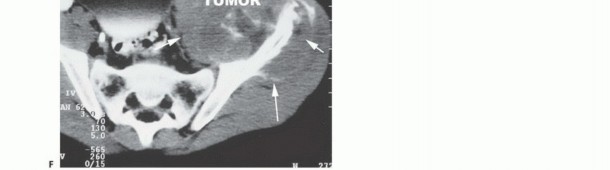

- Computed Tomography (CT): The modality of choice for assessing fine osseous detail, cortical integrity, and matrix mineralization. Thin-slice (≤1 mm) helical CT allows for precise 3D reconstructions. Intravenous contrast is essential to delineate the relationship of the soft tissue mass to major vascular bundles. Chest CT is mandatory for staging to rule out pulmonary metastases.

- Magnetic Resonance Imaging (MRI): The gold standard for evaluating the local extent of the tumor. It accurately defines the intramedullary extent (allowing calculation of bone resection levels), soft tissue extension, joint involvement, and the presence of skip metastases. T1-weighted images best define marrow replacement; T2-weighted and STIR sequences highlight peritumoral edema and the soft tissue mass. Contrast enhancement differentiates cystic from solid components and clarifies neurovascular proximity.